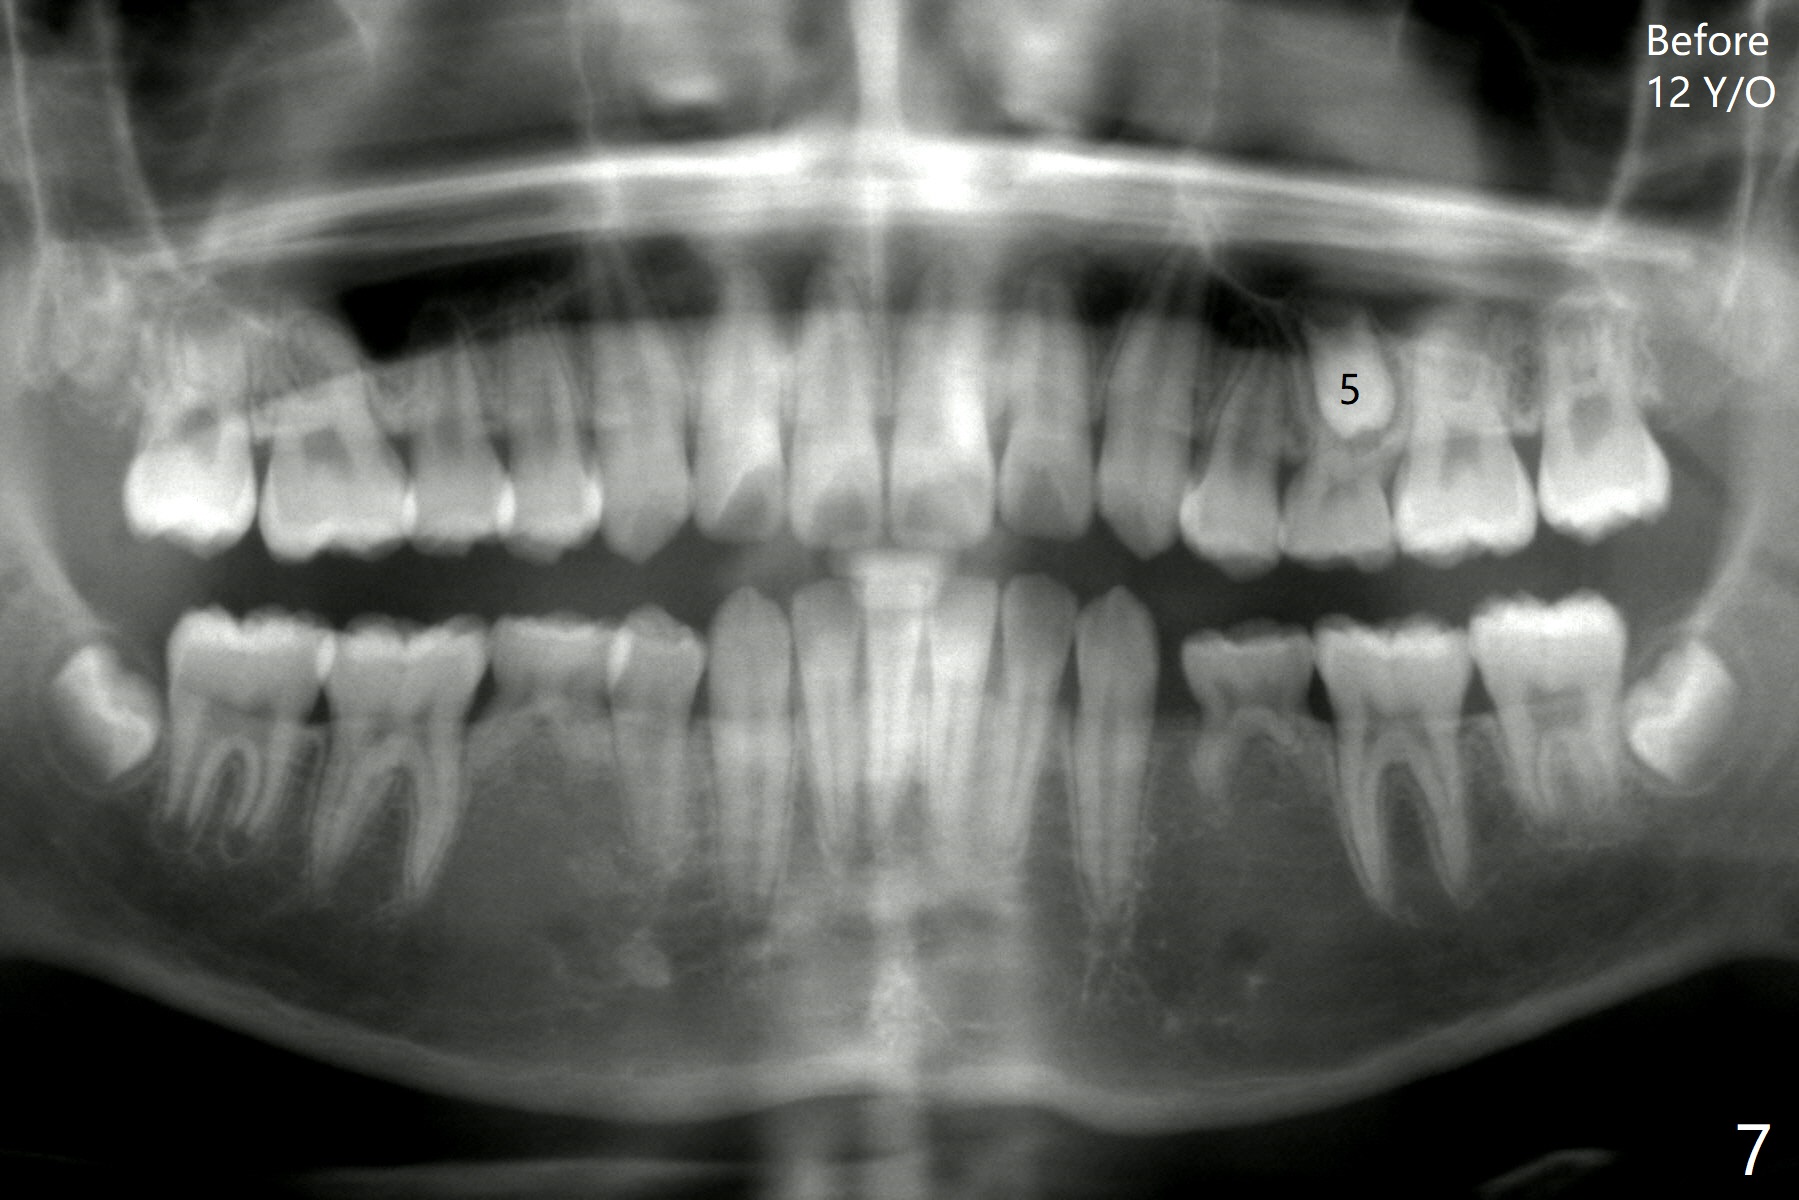

One-year-8-month orthodontic treatment reduces anterior overjet (Fig.1 (double arrows),1', with facial profile improvement), corrects right 1st molar cross bite (Fig.2,2') and dental midlines (Fig.3,3'), closes the diastema between UL3 and 4, extrudes UL5 (Fig.4,5,4',5'), and increases space for future implant at LL4 (Fig.6,6'). In fact large arches with distemata make the treatment possible! Extrusion of UL5 leads to root development (Fig.7, 7' (R)). The increased space at LL4 (Fig.7' *) appears insufficient for an implant.